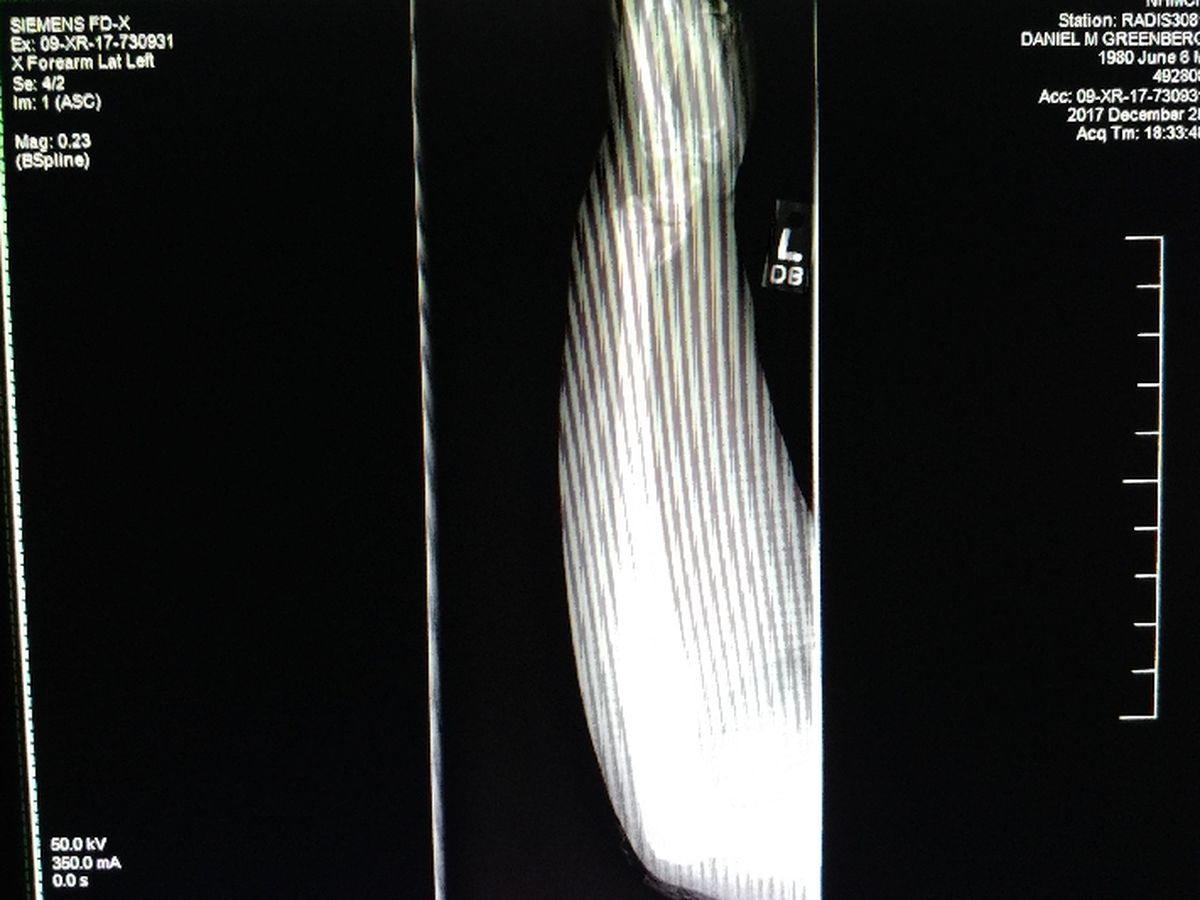

On Christmas I suffered an unfortunate bicycle accident, my body flew head first over the handle bars, I kissed the concrete (bad kisser) and landed on my left arm (not good), resulting in a severe fracture. My left forearm is broken just below the wrist. Not only is it broken, but it's also out of place (really, not good). The wonderful emergency room doctors did everything they could to try and set my bones correctly, but there was only so much they could do.

In order to fix my arm properly, I need an orthopedic surgeon to open me up and put all the pieces back together (ala Humpty Dumpty).